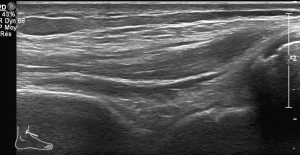

Échographie de la Cheville

Déroulement

La durée de l'examen est d'environ 20 minutes. Il est indolore et est réalisé par un médecin radiologue.